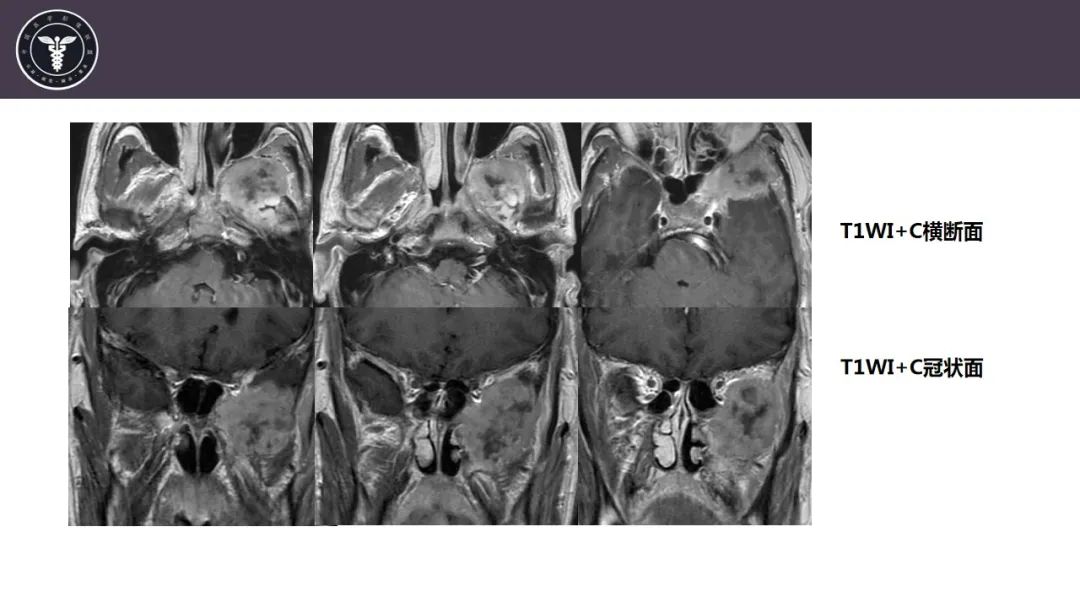

【病例】咬肌间隙肌纤维母细胞肉瘤1例MR诊断与鉴别-4

【病例】咬肌间隙肌纤维母细胞肉瘤1例MR诊断与鉴别-5